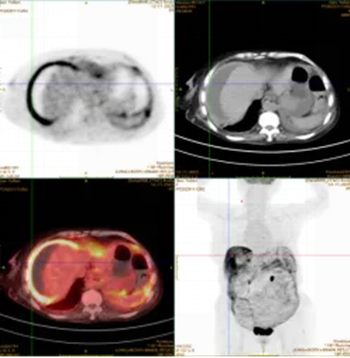

外院曾行诊断性腹腔穿刺,却未能明确病因。PET-CT检查提示恶性肿瘤可能。为寻求进一步诊治,家属来到医院胃肠甲状腺外科找到杨战锋主任。

另一位80岁老年女性患者因精神萎靡、低热就诊,腹部CT检查发现其腹腔积液分布颇具特征:肝脏边缘呈“扇贝形”受压,大网膜增厚呈“饼状”。外院治疗效果不佳,遂至郑大五附院求诊。